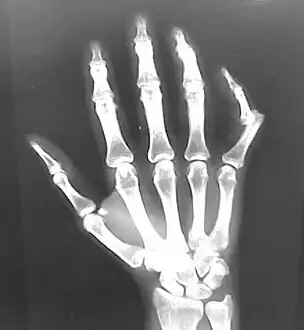

Dislocation of the left index finger

Radiograph of right fifth phalanx bone dislocation- Radiograph of left index finger dislocation